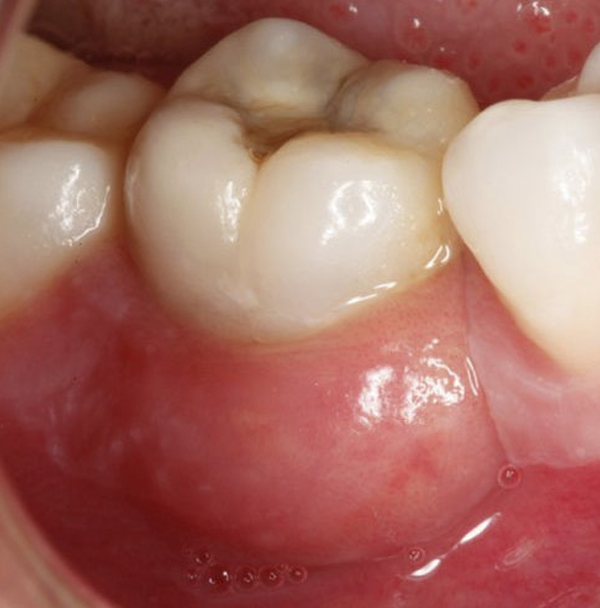

Infección o absceso

en un diente

Es una acumulación de material infectado (pus) en el centro de un diente debido a una infección bacteriana.

Puede ocurrir cuando un diente se rompe o está astillado.

Las aberturas en el esmalte dental

permiten que las bacterias infecten el centro del diente (la pulpa).

La infección puede propagarse

desde la raíz del diente hasta los huesos que lo sostienen.

La infección ocasiona una acumulación de pus e inflamación de los tejidos internos del diente. Esto

causa un dolor de muelas.